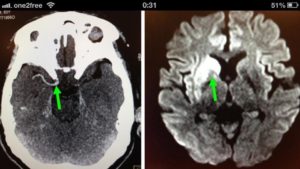

电脑扫描显示罗先生的脑部并没有出血,但电脑扫描不能显示罗先生的颈或脑血管有没有堵塞。要知道电脑扫描对于缺血性中风的诊断帮助是非常有限的,它不能像磁力共振般那样敏感的去侦测病人脑部早期缺血的情况。此外没有注射造影剂的电脑扫描亦不能侦测病人颈部或脑部血管堵塞的情况。当时,磁力共振服务亦不是政府医院中风急救的必须程序,而且政府医院是没有二十四小时的磁力共振造影服务的。

罗先生被送往私家医院的第一步是进行紧急磁力共振造影,报告显示罗先生右边颈和脑部血管大动脉全部都被血栓堵塞着,右边大脑缺血水肿,导致左边手脚冇力和神智半昏迷。经过脑血管外科医生的诊断和急救,在全身麻醉下,医生使用尤如髪丝微细的导管,经过病人右边大腿的腹股沟的大动脉而入,导管再经过腹部和胸腔的大动脉一直向上,游走到病人右边的颈和脑部血管大动脉,进行机械式血栓吸取内血管治疗急救。

经过1小时的血管急救,所有血栓都被移除,罗先生的右颈和脑部血管都给顺利打通,脑部缺血情况立即得到改善。血栓被吸取后, 脑血管外科医生发现罗先生的右颈内动脉有严重血管狭窄的情况,这个狭窄就是罗先生中风的主要原因。医生因此植入血管支架来重新扩张狭窄的血管,以防止罗先生将来中风复发。全身麻醉清醒后,罗先生的大脑意识和手脚活动能力即时好转,他其后再被送回另一间公立医院继续康复治疗。

| 血栓被吸取后, 右颈和脑血管都给顺利打通,脑部缺血情况立即得到改善 | |